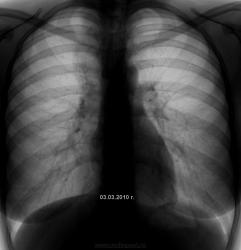

Следовательно, на первом снимке, по правому контуру тени "сердечно-сосудистого массива" тень косы? Если да, то такое может навеять мысли об "исходящем из средостения"?

Игорь Иванович прав, что выставил эти снимки. Волосы у женщин, особенно собраные пучком...приносят немало "сюрпризов"....а если туда еще и люрекса подмешать - коктейль - закачаешся...

Прекрасная иллюстрация. Лаборантов необходимо "фейсом об тейбл".

Я своих заставил все "телепающееся" на голове и шее фиксировать.